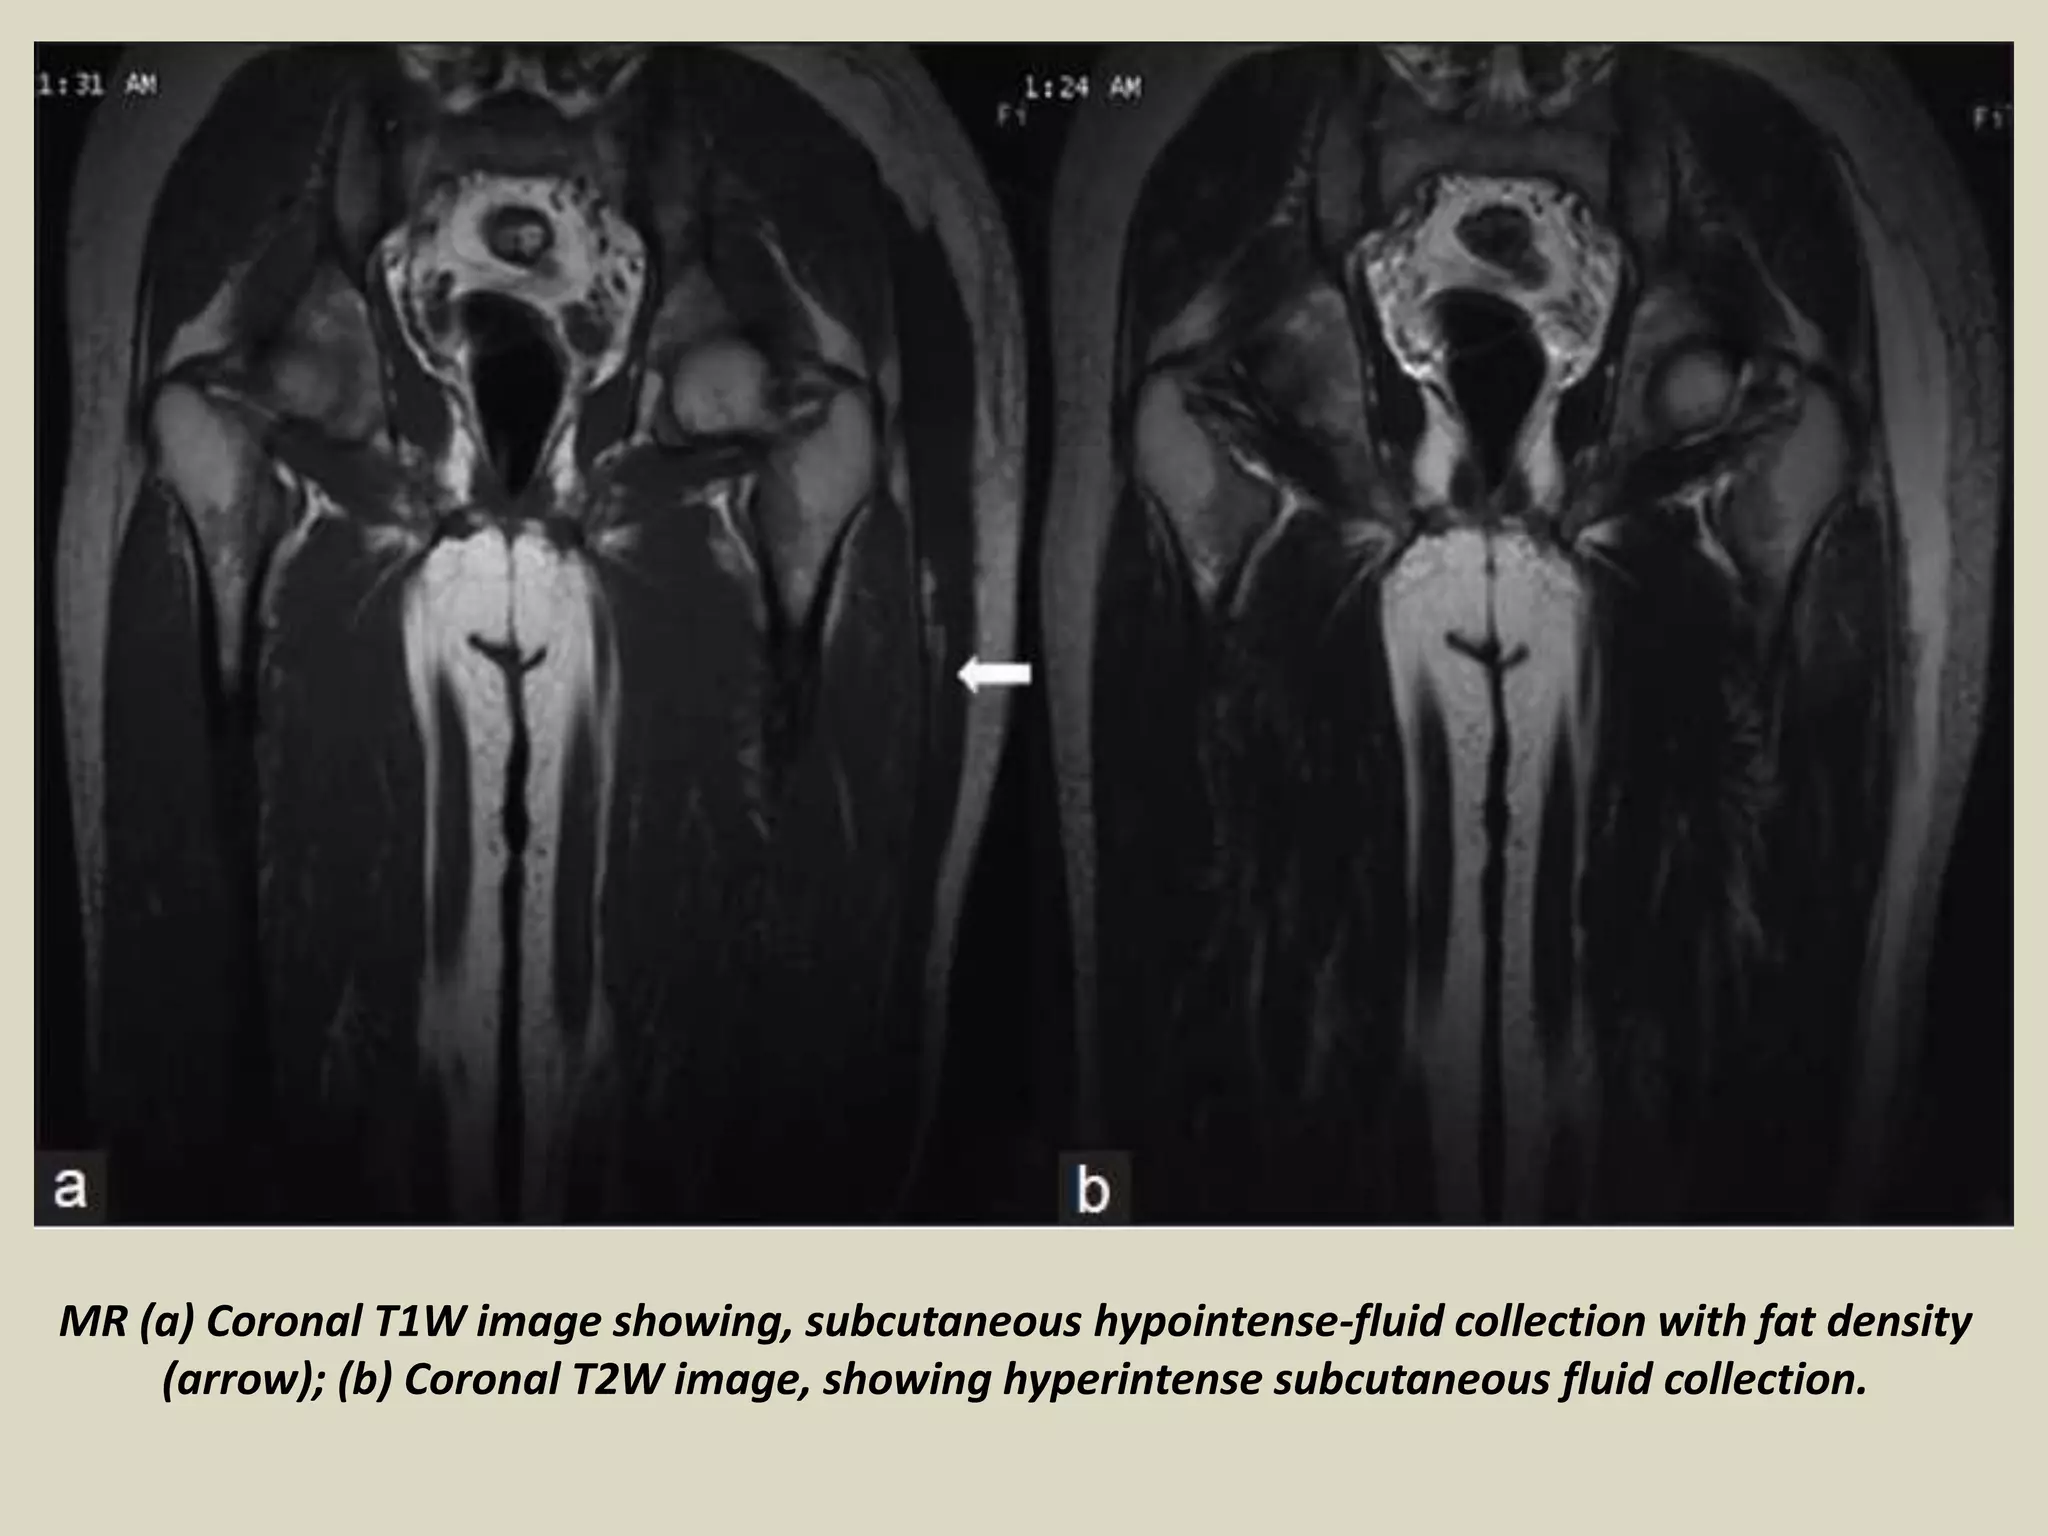

Presentation1, radiological imaging of morel lavallee lesion. Morel Lavallee Lesion Ppt 1 the injury is characterized by the separation of the hypodermis from the underlying fascia and. Submit your diagnosis to see full. An ml lesion is characterized by a traumatic separation of the dermis from the adjacent fascia layer. The lymphatic and vascular structures are. Morel Lavallee Lesion Ppt.

Presentation1, radiological imaging of morel lavallee lesion. Morel Lavallee Lesion Ppt An ml lesion is characterized by a traumatic separation of the dermis from the adjacent fascia layer. The lymphatic and vascular structures are. 1 the injury is characterized by the separation of the hypodermis from the underlying fascia and. Submit your diagnosis to see full. Morel Lavallee Lesion Ppt.

Presentation1, radiological imaging of morel lavallee lesion. Morel Lavallee Lesion Ppt The lymphatic and vascular structures are. Submit your diagnosis to see full. 1 the injury is characterized by the separation of the hypodermis from the underlying fascia and. An ml lesion is characterized by a traumatic separation of the dermis from the adjacent fascia layer. Morel Lavallee Lesion Ppt.

Presentation1, radiological imaging of morel lavallee lesion. Morel Lavallee Lesion Ppt The lymphatic and vascular structures are. Submit your diagnosis to see full. An ml lesion is characterized by a traumatic separation of the dermis from the adjacent fascia layer. 1 the injury is characterized by the separation of the hypodermis from the underlying fascia and. Morel Lavallee Lesion Ppt.

Presentation1, radiological imaging of morel lavallee lesion. Morel Lavallee Lesion Ppt Submit your diagnosis to see full. 1 the injury is characterized by the separation of the hypodermis from the underlying fascia and. An ml lesion is characterized by a traumatic separation of the dermis from the adjacent fascia layer. The lymphatic and vascular structures are. Morel Lavallee Lesion Ppt.

Presentation1, radiological imaging of morel lavallee lesion. Morel Lavallee Lesion Ppt 1 the injury is characterized by the separation of the hypodermis from the underlying fascia and. Submit your diagnosis to see full. The lymphatic and vascular structures are. An ml lesion is characterized by a traumatic separation of the dermis from the adjacent fascia layer. Morel Lavallee Lesion Ppt.

Presentation1, radiological imaging of morel lavallee lesion. Morel Lavallee Lesion Ppt 1 the injury is characterized by the separation of the hypodermis from the underlying fascia and. An ml lesion is characterized by a traumatic separation of the dermis from the adjacent fascia layer. Submit your diagnosis to see full. The lymphatic and vascular structures are. Morel Lavallee Lesion Ppt.